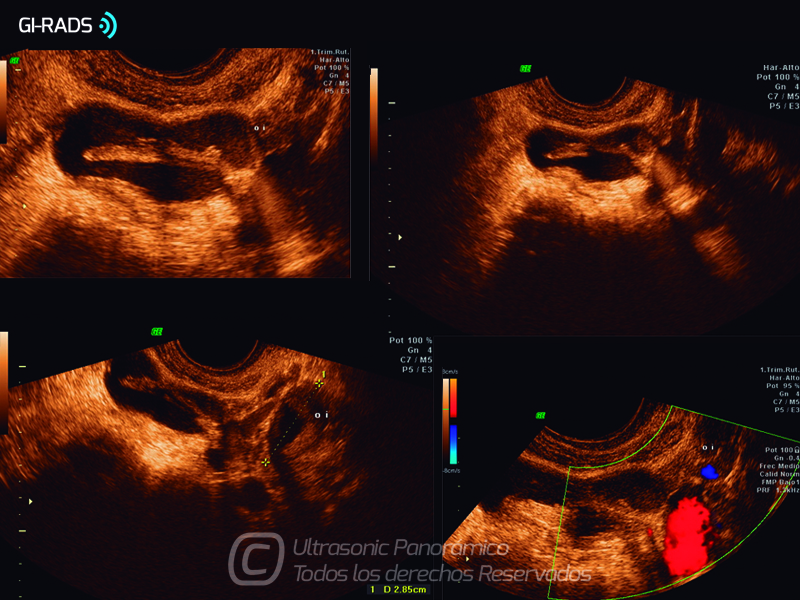

Patologías Benignas – Abceso Tubo Ovárico

• Patologías Benignas – Abceso Tubo Ovárico